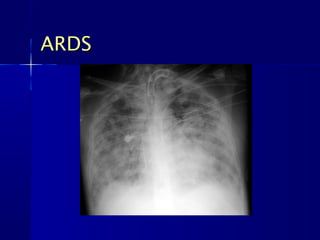

ARDSARDS



CXR CHARACTERISTICSCXR CHARACTERISTICS

– Normal size heartNormal size heart

– No pleural effusionNo pleural effusion

– Ground GlassGround Glass appearanceappearance

– Often normal early in the disease but may rapidlyOften normal early in the disease but may rapidly

progress to complete whiteoutprogress to complete whiteout